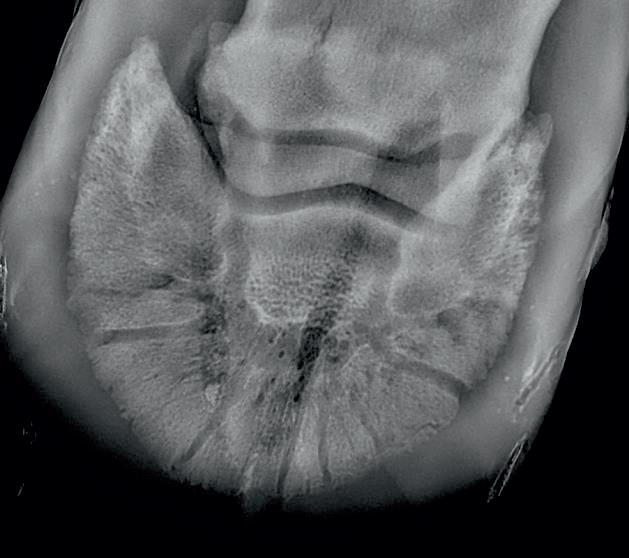

Radiographic proof in clinical results

BONE Gold nutritional bone joint and collagen supplement was formulated to provide some of the essential amino acid requirements of collagen type I, II and III (found in bone and connective tissue) in addition to supporting the nitric oxide pathway which has been found to assist in the formation of bone callus postinjury.

Veterinary surgeons have recommended that Bone Gold may assist with sore shins, tendon injuries, ligament injuries, osteoarthritis and post-surgery in horses and polyarthritis, geriatric osteoarthritis, and post-surgery in dogs.

Here is a veterinary radiographic report on a horse with a fracture evident on the medial toe and after treatment and feeding Bone Gold during this period. More information on these products can be found at www.vetgold.com.au

VETERINARY RADIOGRAPHIC REPORT

HORSE: "XXXXXXXX"

DATES OF EXAMINATION: 26TH AUG, 21ST OCT 21 & 17TH NOV '21

HORSE: “XXXXXXXX”

PLACE: XXXXXXXXXX FARM

DATES OF EXAMINATION: 26TH AUG, 21ST OCT 21 & 17TH NOV ‘21

XXXXXXX's left and right front feet were radiographed on 26th Aug, 21st Oct (8 weeks) and again on the 17th Nov '21(12 weeks).

XXXXXXX’s left and right front feet were radiographed on 26th Aug, 21st Oct (8 weeks) and again on the 17th Nov ‘21(12 weeks).

RADIOGRAPHS:

26.08.21: Right Front: Large P3 solar margin fracture evident on medial toe 32.6mm x 4.1mm with approximately 1.4mm separation from parent bone as below left image.

21.10.21: Right Front: Fine residual 4.2mm fracture still evident, approximately 90% resolution

17.11.21: Right Front: Fracture fully resolved

26TH AUG 21

21ST OCT 21

RECOMMENDATIONS:

Radiographic results as of the 17th Nov '21 show total resolution of the original fracture.

XXXXXXX was reshod today utilising off an alloy shoe with a toe clip - inner circumference seated out to avoid any sole pressure. The horse can return to training.

Please do not hesitate to contact me if you have any further queries

COMMENTS:

Solar margin Type IV fractures of this magnitude have well-documented internationally published healing rates of 7 - 12 months. Full resolution of these fractures is rare as most often the fracture fragments are resorbed. Full resolution in a 3 month period was not anticipated.

The horse was on Bone Gold 3 x scoops fed once per day for this period.

26th August 2021 21st October 2021 17th November 2021